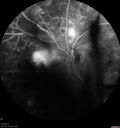

Proliferative diabetic retinopathy with vitreous hemorrhage181 views53 year old man with foggy vision in the left eye for one day. VA 20/25 OD, 20/40 OS. Diabetes for 10 years. Type IISep 16, 2023

Proliferative diabetic retinopathy with vitreous hemorrhage164 views53 year old man with foggy vision in the left eye for one day. VA 20/25 OD, 20/40 OS. Diabetes for 10 years. Type IISep 16, 2023

Proliferative diabetic retinopathy with vitreous hemorrhage167 views53 year old man with foggy vision in the left eye for one day. VA 20/25 OD, 20/40 OS. Diabetes for 10 years. Type IISep 16, 2023